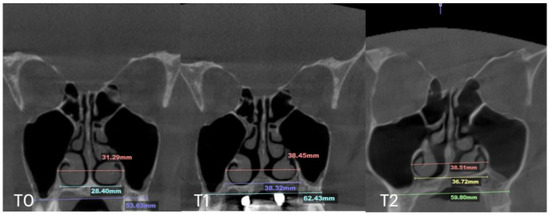

| Nasal Base Width, mm | Maxillary Base Width, mm | Lateral Nasal Width, mm | Inter-Pterygoid Distance, mm | Midpalatal Suture Separation, mm | |||||||||

|---|---|---|---|---|---|---|---|---|---|---|---|---|---|

| T0 | T1 | T2 | T0 | T1 | T2 | T0 | T1 | T2 | T0 | T1 | T2 | T1 | |

| Case A | 30.84 | 38.15 | 38.37 | 59.22 | 66.37 | 67.11 | 32.8 | 39.33 | 39.48 | 28.01 | 32.88 | 33.38 | 10.5 |

| Case B | 30.61 | 34.41 | 34.97 | 59.73 | 63.47 | 60.56 | 31.79 | 34.6 | 35.35 | 29.18 | 31.38 | 34.59 | 5.7 |

| Case C | 28.40 | 38.32 | 36.72 | 53.63 | 62.43 | 59.80 | 31.29 | 38.45 | 38.51 | 29.15 | 35.8 | 35.36 | 8.47 |

| Case D | 26.25 | 33.27 | 31.54 | 55.9 | 61.84 | 60.37 | 33.98 | 35.94 | 38.09 | 29.77 | 29.24 | 29.02 | 6.2 |